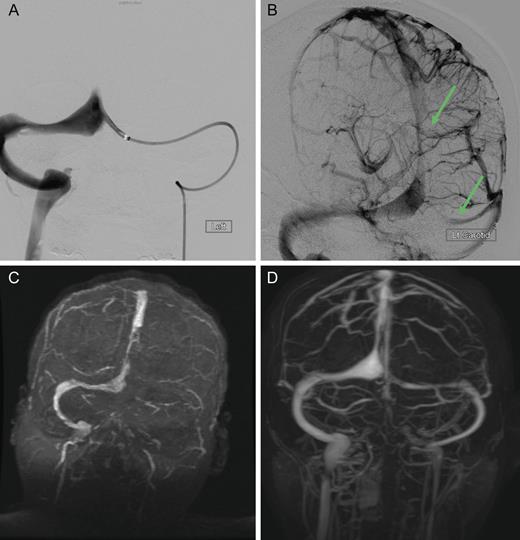

Axial MRI demonstrating cerebral tissue injuries from venous hypertension with the associated ischemia: (A) Diffusion-weighted imaging (DWI) MRI. (B) Fluid-attenuated inversion recovery (FLAIR) imaging. (C) T2-weighted MRI. (D) Gradient-echo (GRE) imaging.

Cranial computed tomography (CT) demonstrated subtle hypodensity mainly in the left occipital lobe, with a characteristic empty delta sign (Fig. 1). Computed tomography angiography demonstrated normal filling of the posterior cerebral arteries (PCA). Cranial magnetic resonance imaging (MRI) evaluations demonstrated bilateral ischemic changes involving the occipital and parietal lobes, more extensively on the left (Fig. 2). Magnetic resonance venography (MRV) demonstrated complete occlusion of the left transverse and sigmoid sinuses, as well as near occlusion of the posterior superior sagittal sinus (Fig. 3C).